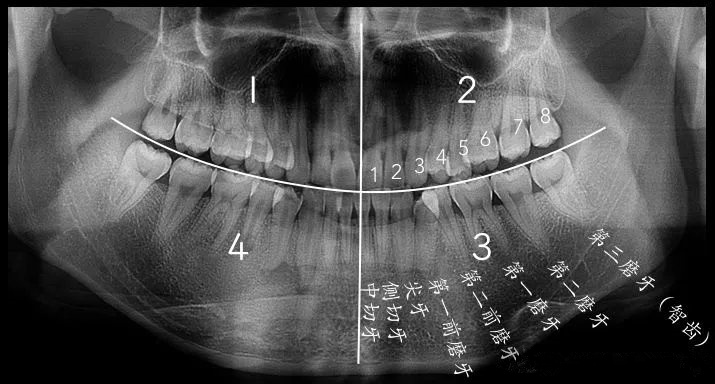

有沒有智齒,肉眼無法判斷的話,拍個(ge) 全景片一看便知

不同的立世牙

如圖所示,難度大的阻生智齒拔牙,可能無法整顆取出,而是要把智齒切割為(wei) 幾個(ge) 部分後再取出